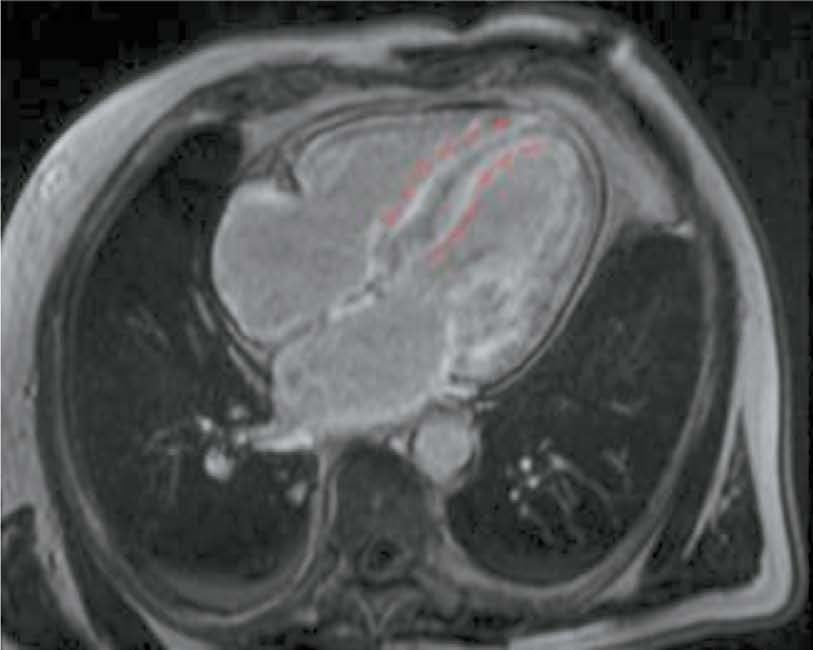

AIM: The aim of this study was to evaluate the capabilities of cardiac magnetic resonance imaging in the differential diagnosis of cardiomyopathies due to AL and ATTR amyloidosis.

MATERIALS AND METHODS: A retrospective analysis of the medical records of 25 patients with a confirmed diagnosis of amyloid cardiomyopathy was performed. Patients were divided into two groups according to the type of amyloidosis, with group 1 including patients with cardiomyopathy due to AL amyloidosis and group 2 including patients with cardiomyopathy due to ATTR amyloidosis. All patients underwent contrast-enhanced cardiac magnetic resonance imaging. Volumetric and linear cardiac parameters, ventricular function, and late gadolinium enhancement patterns were assessed. Standard statistical methods were used, and differences were considered significant at p <0.05.

RESULTS: Group 2 showed a more significant thickening of the myocardial walls compared to group 1 (interventricular septum: 18 [17; 18] vs. 14.5 mm [12.8; 16.0], p <0.01, posterior wall of the left ventricle: 14 [13; 17] vs. 10.5 mm [10; 12.3], p <0.01). The indexed mass of the left ventricle myocardium was 110 [92; 125] in group 2 and 85 mm [69.3; 91.8] in group 1 (p <0.01). In group 2, late gadolinium enhancement with a transmural left ventricle pattern was more frequently observed in the basal and mid-lower-lateral segments, whereas in group 1, a subendocardial pattern of late gadolinium enhancement was more frequent in the mid-anterior and lower-lateral segments (p <0.05). In addition, frequency of simultaneous contrast enhancement in the subendocardial layers of the interventricular septum on the left ventricle and right ventricle sides was higher in group 2 (100% of cases vs. 50%, p <0.01). Late gadolinium enhancement of the right ventricle was also more common in group 2 (100 vs. 58%, p <0.05), especially in the interventricular septum and inferior wall area (p <0.05). Semi-quantitative assessment of LGE using the Query Amyloid Late Enhancement (QALE) showed greater contrast enhancement in group 2: 13 [12; 14] vs. 10.5 [1.75; 12], p <0.01), and a score greater than 13 differentiated between cardiomyopathy due to AL amyloidosis and ATTR amyloidosis with a sensitivity of 69% and a specificity of 83%.

CONCLUSIONS: Cardiac MRI identifies typical features of cardiomyopathies due to AL amyloidosis and ATTR amyloidosis for their differential diagnosis. Further research is needed to confirm diagnostic accuracy of the patterns identified.